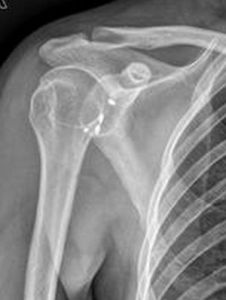

X線徵象是構成肩關節的肩腫骨、肩盂和肱骨頭的兩關節面失去正常平行的關係。按肱骨頭分離的程度和方向,分為以下幾型:

1.肩關節半脫位

關節間隙上寬下窄。肱骨頭下移,尚有一半的肱骨頭對向肩盂。

2.肩關節前脫位

最多見。其中以喙突下脫位尤為常見。正位片可見肱骨頭與肩關節脫位

肩盂和肩胛頸重疊,位於喙突下0.5cm-1.0cm處。肱骨頭呈外鏇位,肱骨幹輕度外展。肱骨頭鎖骨下脫位和盂下脫位較少見。

3.肩關節後脫位

少見。值得注意的是正位片肱骨頭與肩盂的對位關係尚好,關節間隙存在,極易漏診。只有在側位片或腋位片才能顯示肱骨頭向後脫出,位於肩盂後方。